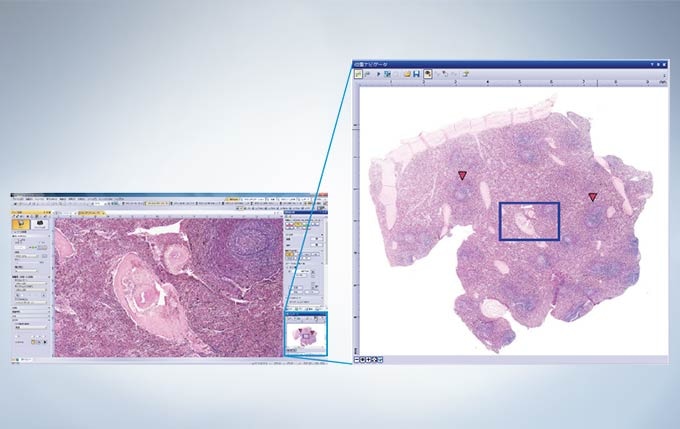

Easily know the location of interest with the Position Navigator

The position navigator adds convenience to the operator’s workflow because it creates a map to help users keep track of their location within the specimen; this is especially useful when making observations at high magnification. This is achieved without the need for a motorized or encoded stage. The low-magnification map of the sample containing all of the pertinent location information can be stored along with the high-magnification observation image, making it convenient for record keeping or creating presentation materials. *The accuracy of the map creation and the position navigation depends on observed samples...

Context Map And High-Magnification Images Stored in a Single File

The metadata images used in the camera’s mapping feature can also be used as stand-alone images. In addition, the entire overview map and high-magnification image can be saved and exported in a common file format for enhanced flexibility. Users are able to place markers in real-time on the overview map to highlight potential areas of interest, making it easy to go back and re-image previously viewed areas.